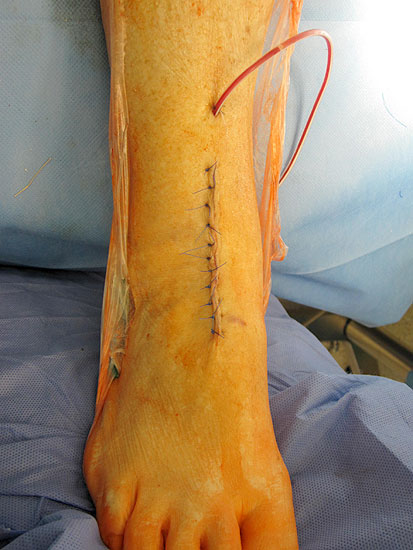

Osteosynthese eines intraoperativ frakturierten medialen Malleolus mit perkutanen Schrauben.

Abbildung 19

1. intraoperative Innenknöchelfraktur:

Mögliche Ursachen können eine zu weit medial plazierte Tibiakomponente oder eine zu weit mediale, nicht nach lateral konvergierende Sägerichtung im Rahmen der ventrodorsalen distalen Tibiaresektion sein (Abb. 19).